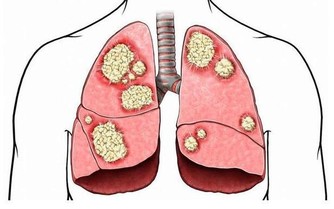

答:氯氣對人體有嚴重危害,它能刺激眼、鼻、喉以及上呼吸道等。引起急性肺水腫及肺炎,濃度高時可麻痹呼吸中樞、出現「閃擊性死亡」。長期吸入低濃度的氯會引起慢性中毒,導致體內產生大量的自由基,加速人體衰老速度。主要病癥為鼻炎、慢性支氣管炎、肺氣腫、肝硬化、動脈粥樣硬化,甚至是癌癥。

氯加入水中後,會讓您的頭發產生幹澀、斷裂、分叉,也讓您的肌膚漂白化、皮膚層脫落及產生奇癢無比的皮癬過敏癥。氯受熱後與水中有機腐質產生三氯甲烷等致癌物質。

答:將自來水加以煮沸,氯受熱後與水中有機腐質產生三氯甲烷等致癌物質,三氯甲烷將比自來水增加3~4倍,如果餘氯不能去除,我們每日所飲用的咖啡、茶或湯,經加溫煮沸飲用後;我們的體內即增加了3~4倍的致癌物。

10.長期飲用含餘氯的水會導致什麽疾病?

答:心臟疾病、冠狀動脈粥樣硬化、貧血癥、膀胱癌、肝癌、直腸癌、高血壓和過敏等癥狀。